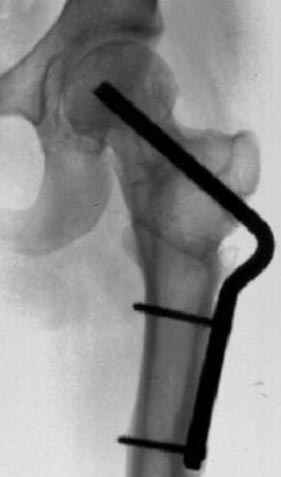

Несколько снимков из моей коллекции, чтобы разьяснить, почему мы до сих пор делаем различные варианты остеотомии.

На рисунке N1 предоперационный план лечения ложного сустава шейки бедра- линия ложного сустава, угол и направление введения импланта, клиновидная остеотомия в градусах и миллиметрах, второй снимок после коррекции, расчет, на сколько удлиняется конечность и размеры импланта;

N3 рисунок окончательный снимок, после операции моя рентгенограмма должен выглядеть примерно как эта картина. На N4 снимке клин перед удалением; N5 послеоперации 3 нед.; N6 окончательная рентгенограмма.

варус при проксимальном отделе 95 градусной пластиной.